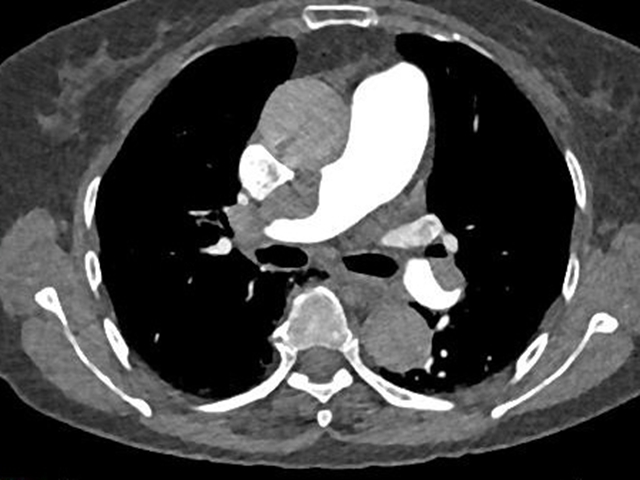

张三的家人迅速将他送往西南医科大学附属中医医院,这一举动挽救了他的生命。接诊医生通过对症状的判断迅速启动了胸痛三联征“一站式”CT检查(这是一种通过注射造影剂进行的CT检查技术,可以详细观察胸部大血管的结构)。

经过检查,医生迅速诊断出张三患有主动脉夹层,需要立即行手术干预。最终张三接受了手术治疗,成功挽救了生命。如果没有及时的“一站式”CT检查,他的情况会迅速恶化,将危及生命。

“一站式”CT检查

胸痛三联征“一站式”CT检查是指通过一次扫描、一次注射造影剂可同时显示冠状动脉、肺动脉及主动脉三种血管的图像,有助于早期、快速诊断,同时可以最大程度降低辐射剂量。因此已成为目前评估急性胸痛患者的首选检查方法。